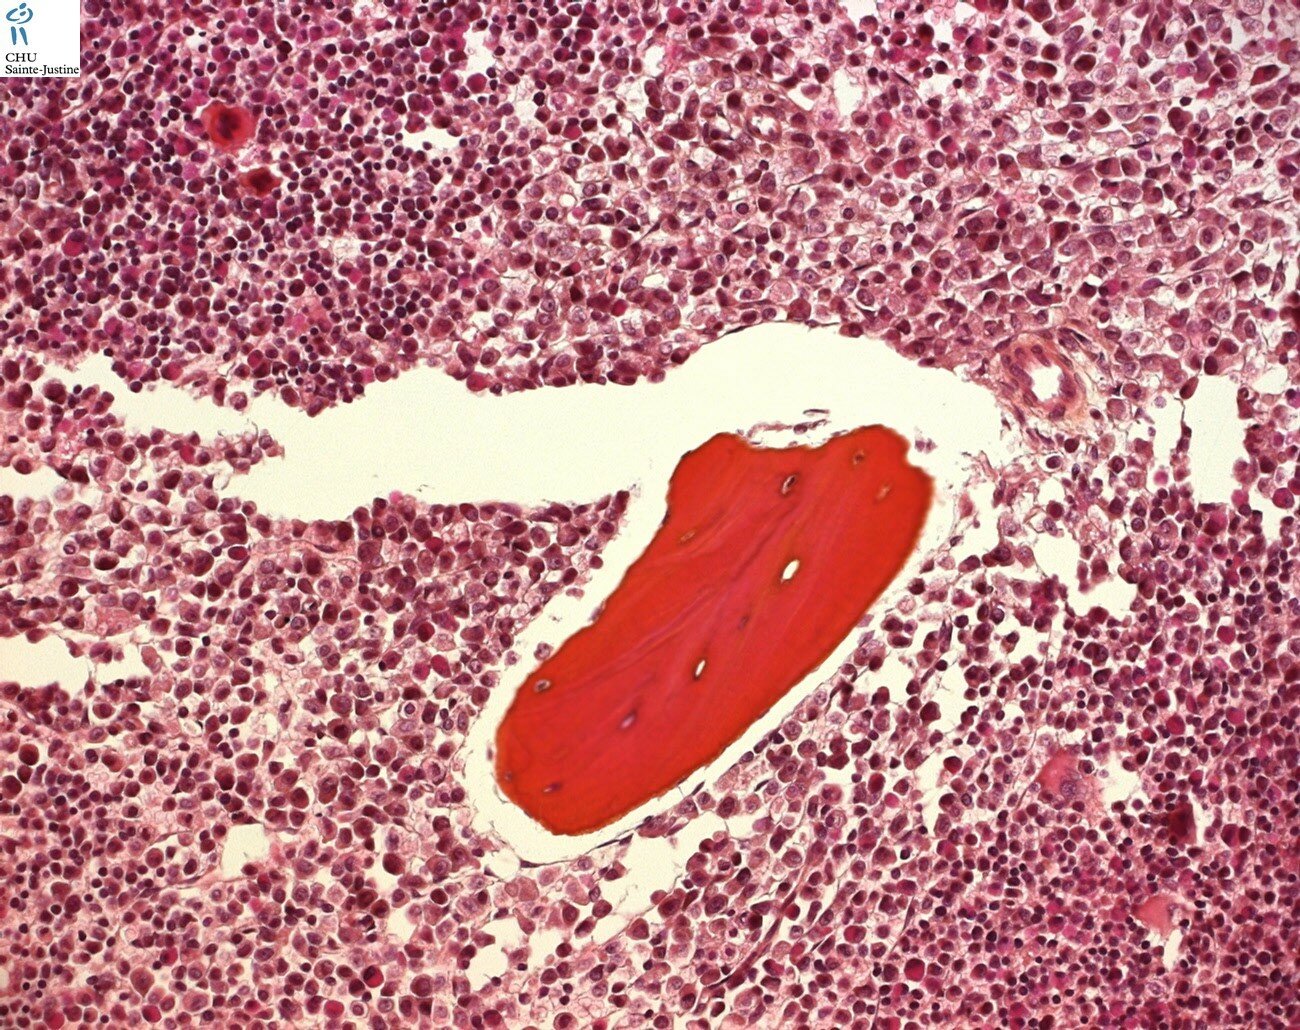

Morphology